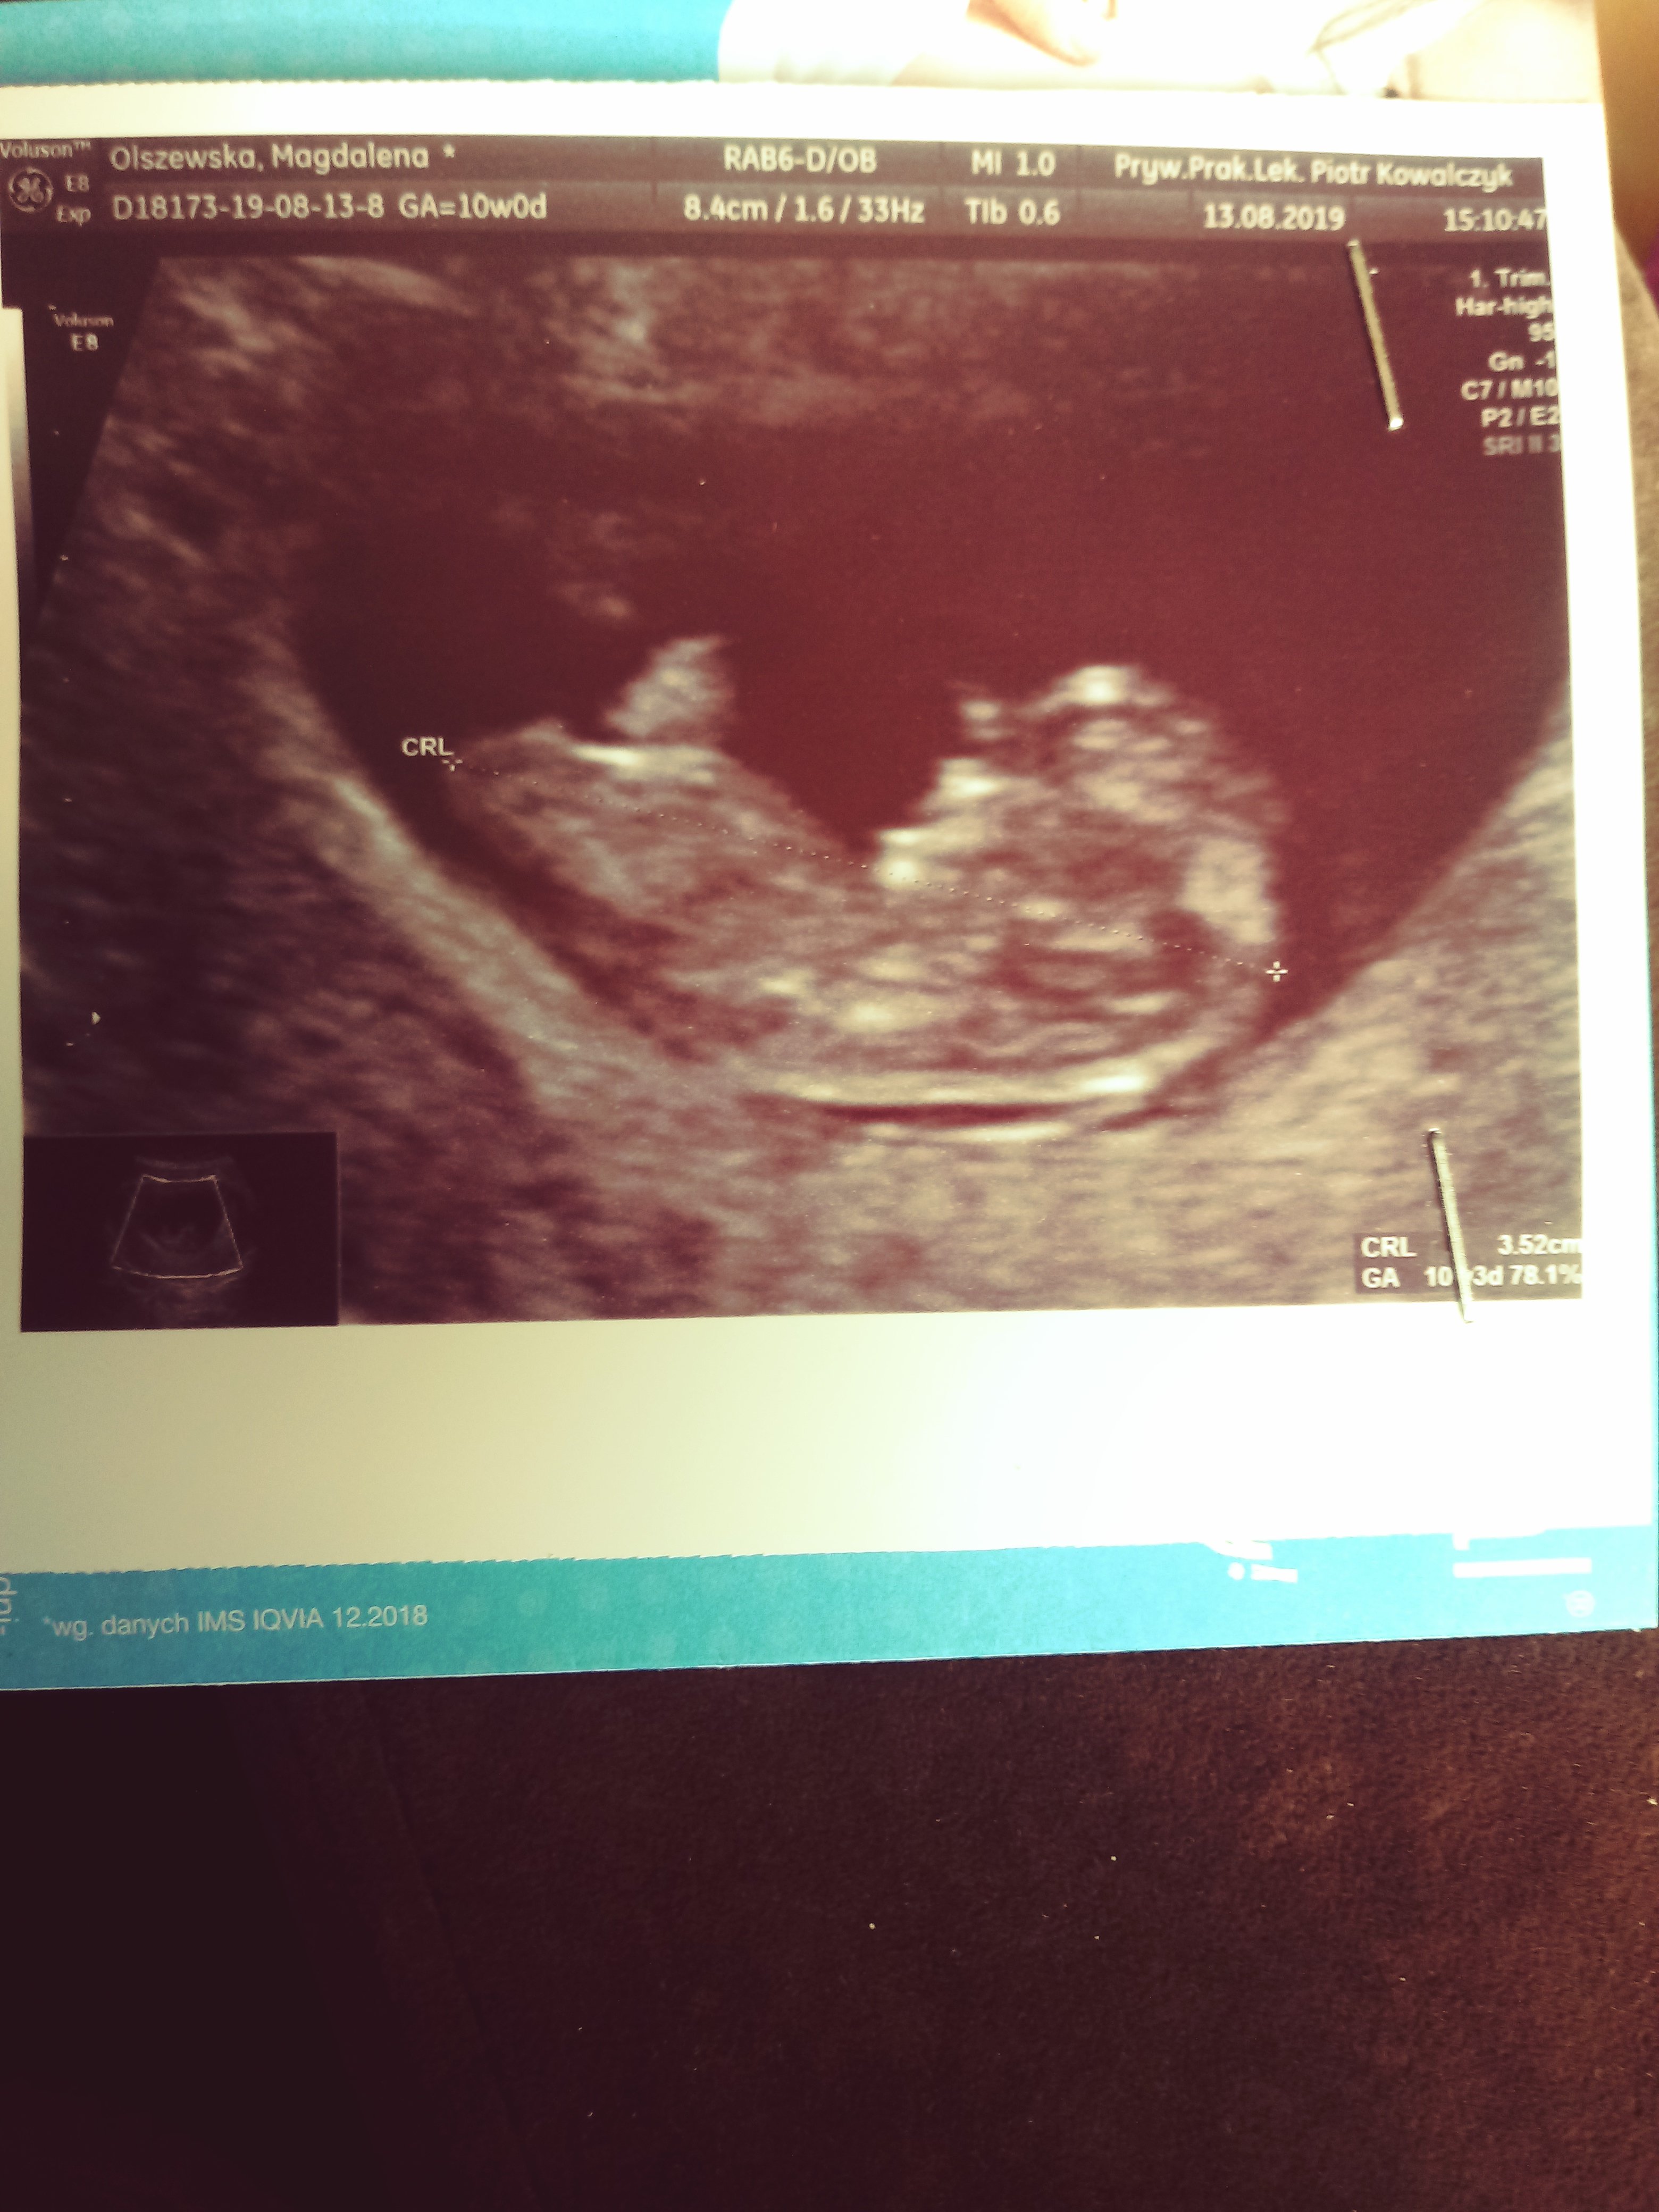

Dziewczyny przepraszam ale jeszcze dopytam o to usg. 5 dni temu 3 mm, dzisiaj 5 mm no jak zapytałam czy tylko to zmierzył i 7 mm. Niby tak jak wg Om prawie (minus jeden dzień) ale mnie to niepokoi :(

Załączniki

• 20190813_173619.jpg

20190813_173619.jpg

1 021,3 KB · Wyświetleń: 145